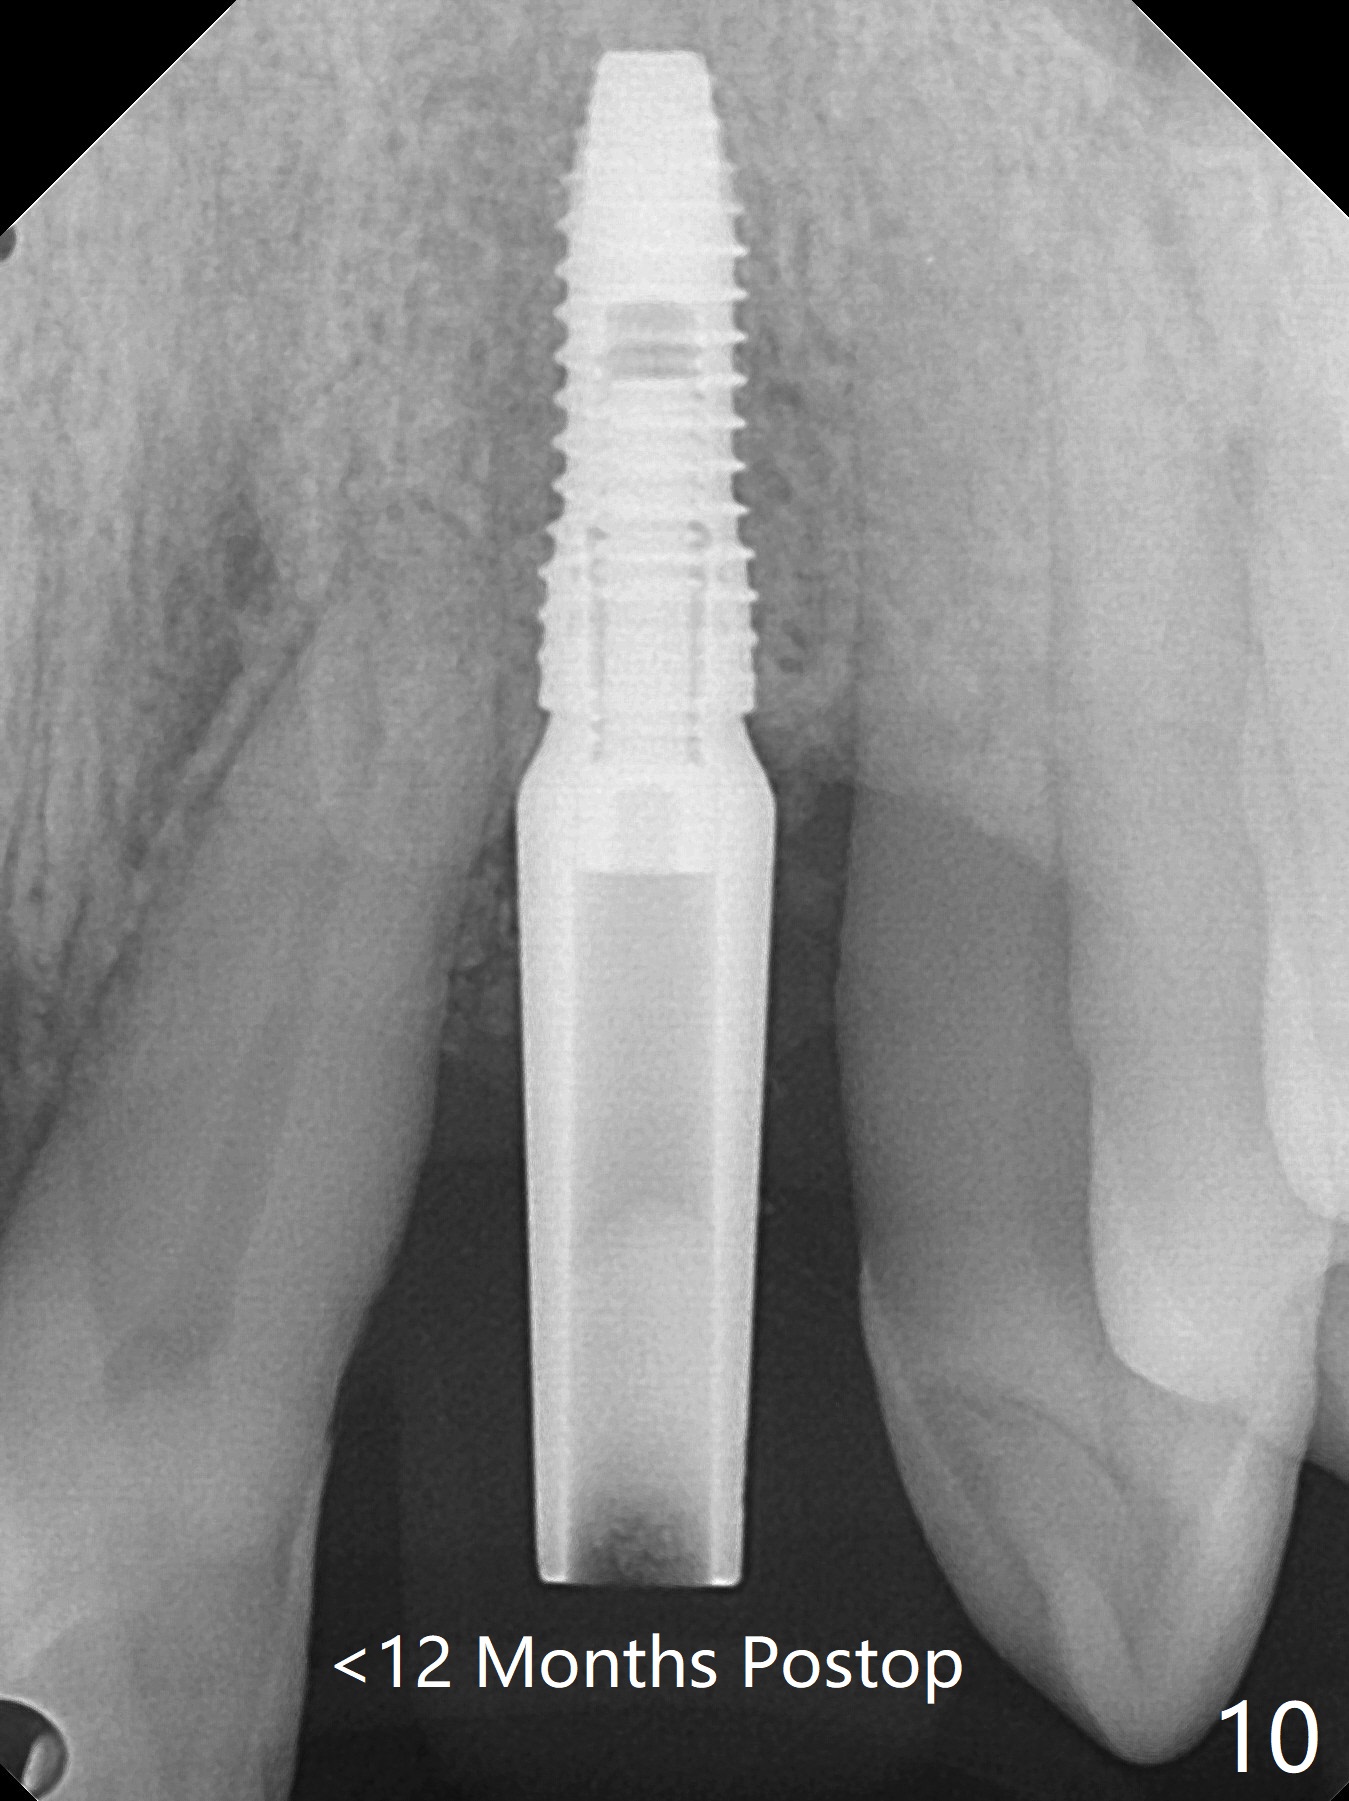

实验结果表明红管抽取上清液形成粘性骨块比白管快。左上二拔除,即刻徒手钻洞(图一),初步植入3.8x11.5毫米植体(图二),调整植体深度,然后放置直径4.5毫米长基台(图三,DIO UF; 牙龈厚度大于6毫米),最后填入大量粘性骨粉(图四,五 *),植体颊侧近中骨粉不足(图五 ^),之后再次充填骨粉。制作即刻修复物,颊侧瘘道和牙槽窝开口放置PRF膜。术后三周临时牙冠松动,取出后者,颊侧空间有两个区域:牙龈和骨粉(图六:白,黑星号)。由于脑部手术,术后接近一年病人回来取模。由于基台长,临时牙冠还没有脱落(图八)。牙龈袖正常(图九:*)。术后一年骨粉仍在植体,基台交界处(图十)。